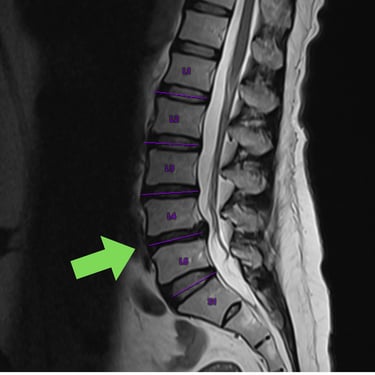

Listesis Lumbar: Artrodesis con Tornillos Transpediculares y Fusión Intersomática Transforaminal (TLIF).

La listesis lumbar es el deslizamiento anormal de una vértebra sobre otra, lo que puede generar dolor lumbar crónico, inestabilidad y compresión de las raíces nerviosas. Cuando el tratamiento conservador no es suficiente, la artrodesis con tornillos transpediculares (FTP) asociada a la fusión intersomática transforaminal (TLIF) es una técnica quirúrgica efectiva. Este procedimiento permite estabilizar la columna, restaurar la alineación vertebral y lograr una fusión sólida, al mismo tiempo que descomprime las estructuras nerviosas. La combinación de estas técnicas mejora el control del dolor, la función neurológica y la calidad de vida del paciente.